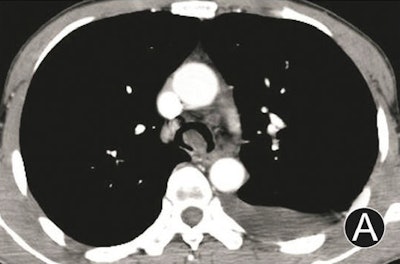

- Intraluminal and extraluminal tumors: These manifest as infiltrated growth along thickened walls, with invasion extraluminally, and masses both intraluminally and extraluminally.

Tumors with dominant intraluminal growth have significant luminal stenoses, the group noted. Tumors with evident extraluminal growth may resemble mediastinum tumors. Tumors with apparent intraluminal and extraluminal growth have large masses and are often obstructive.

- Tumor morphologies (2 endoluminal nodes with narrow bases, 13 endoluminal nodes with wide bases, and 16 both intramural and extramural masses)